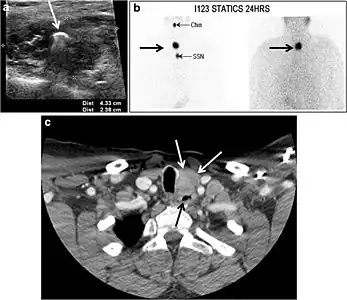

Fig. 8. A 48-year-old male patient post total thyroidectomy with PTC recurrence. a Transverse greyscale ultrasound of the neck demonstrates a left thyroid bed heterogeneous, predominantly hypoechoic irregular lesion with calcifications (white arrow). b A spot image of iodine 123 total body scan of the neck demonstrate a focus of abnormal radiotracer uptake at the left thyroid bed (Black arrows) between the annotated markers. c Enhanced axial CT scan of the neck demonstrates an enhancing large left thyroid bed mass (white arrow) with no calcifications. The lesion exerts a mass effect on the oesophagus (black arrow) and is inseparable from the trachea.[1]